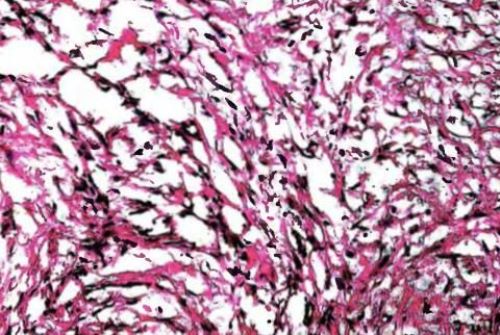

При исследовании под микроскопом злокачественное образование будет выглядеть как ограниченный инкапсулированный узел, в большинстве случаев имеет крупнобугристую поверхность. Если она исходит из крупного ствола нервов, то он будет выглядеть утолщённым с веретенообразным рельефом. Отделит его от опухоли практически невозможно. В разрезе ткань шванномы будет серого или желто-белого цвета, блестящая с волокнистой структурой или напоминающей желатин. Если форма низкодифференцированная, волокнистости может не быть, тогда опухоль будет иметь вид «рыбьего мяса».

Клетки опухоли имеют удлиненную форму и вытянутые ядра. Клетки расположены пучками, направленными в разном направлении. Ядра отличаются полиморфностью и гиперхромностью, в них присутствуют митозы. Злокачественные шванномы принято различать по степени зрелости и соотношению клеточных и волокнистых элементов.